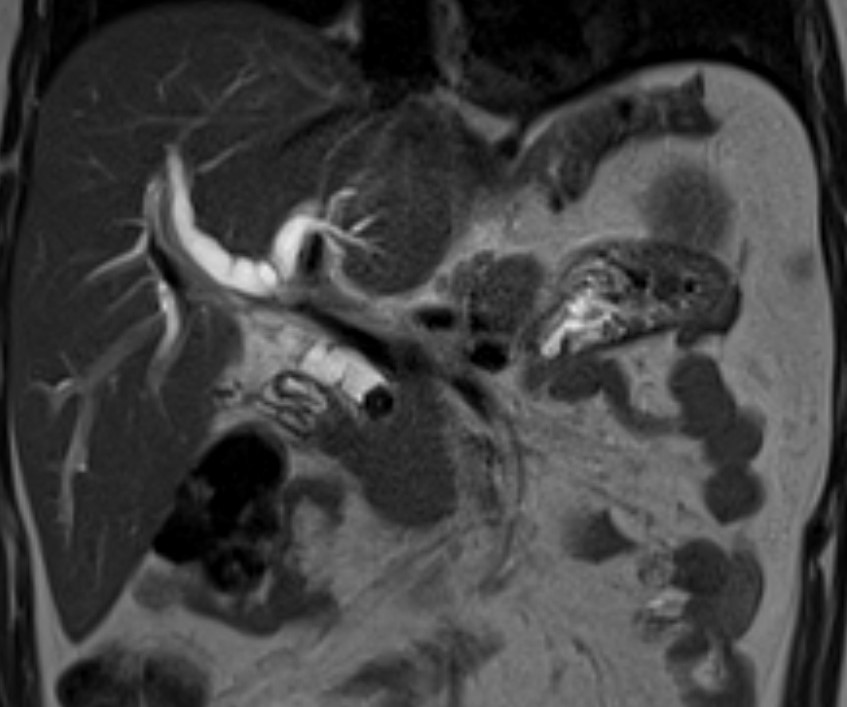

Our Post CCT/Senior Complex Benign PB & Robotic Fellowship at @UHDBTrust is now open for applicants to start from Aug 2026.

Gain experience in advanced laparoscopic and robotic benign PB surgery. In addition, fellows will develop skills in laparoscopic and robotic hernia surgery including complex abdominal wall hernias as well as training in ERCP.